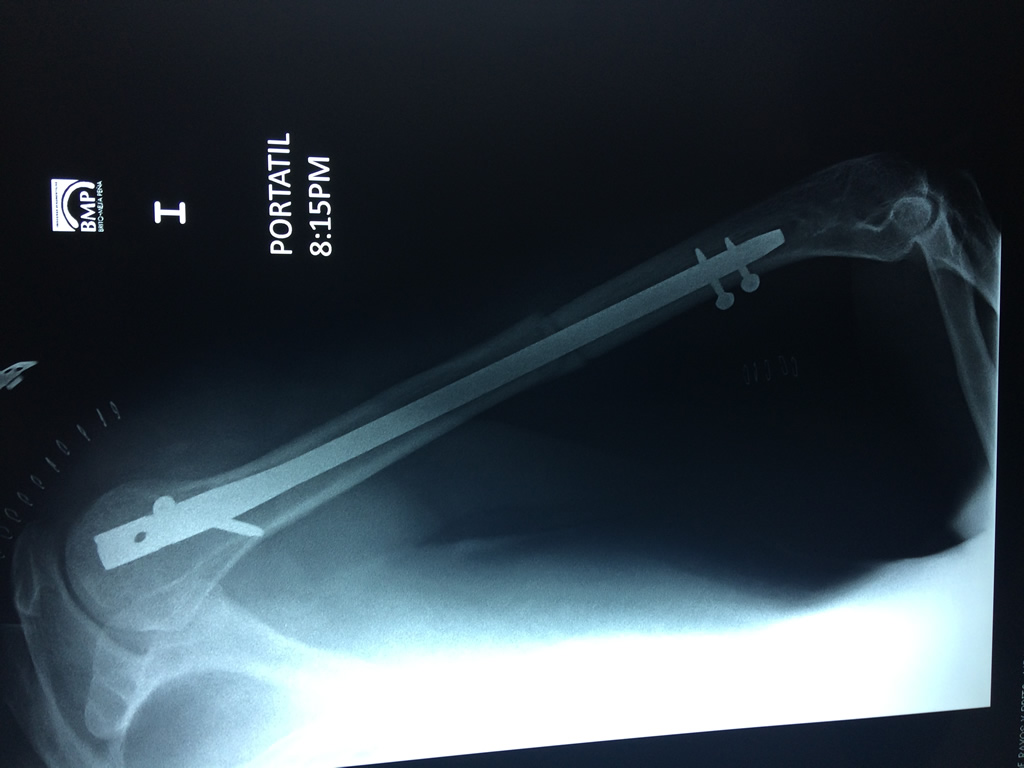

Cirugías de Muñecas

El Húmero (en latín, humerus) es el hueso más largo de las extremidades superiores en el ser humano. Forma parte del esqueleto apendicular superior y está ubicado en la región del brazo. ... El extremo proximal del húmero tiene la cabeza, cuellos quirúrgico y anatómico y tubérculos mayor y menor.